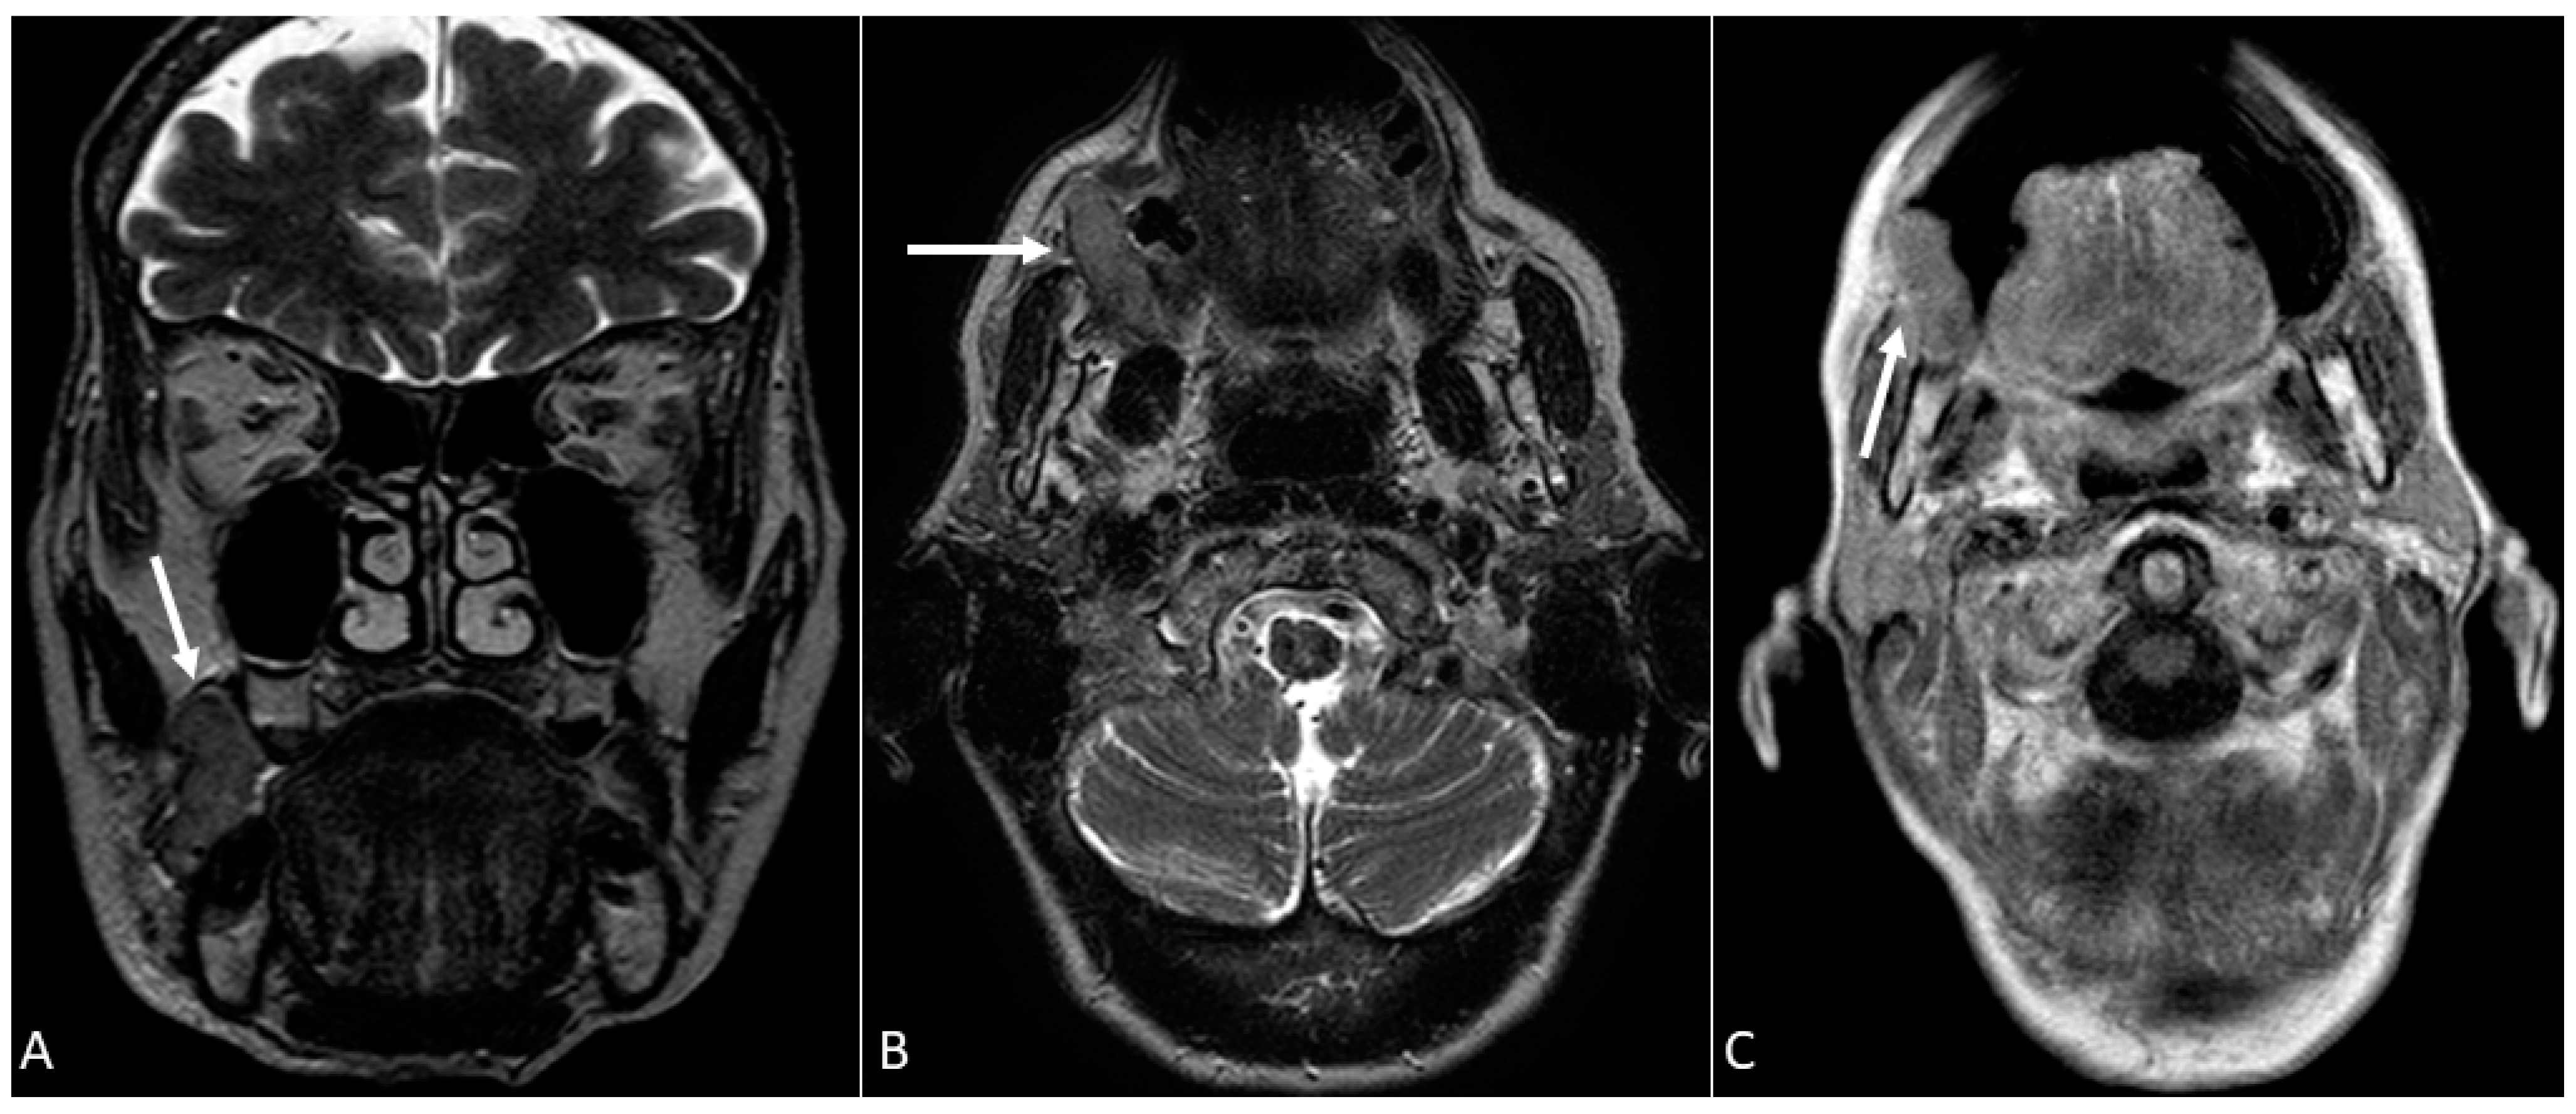

- Open mouth technique. Patients open their mouth and the acquisition is obtained with quiet respiration. A device (i.e., a 50 mL syringe) can be used between teeth to ensure the maintenance of the right position [28]. It allows the separation of the palatal mucosa from the muscular component of the tongue clarifying the exact origin, infiltration, and thickness of tumoural masses (Figure 12 and Figure 13).